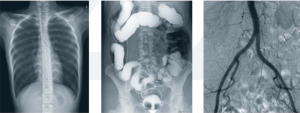

PLD9600動態平板DRF醫用診斷X射線機具備數字透視、數字點片攝影和數字DR攝影功能,利用它可以進行胸部和腹部透視、消化道造影、泌尿生殖系統造影、膽道造影以及下肢靜脈等多種造影;可以進行頭顱、胸部、腹部和四肢等部位的DR攝影;也可用於在透視下進行骨折整復、取異物等;可用於開展周邊血管造影和介入治療。

本款動態平板DRF是一款放射科設備精品,在醫療器械領域占據重要地位,該設備具備數字透視、數字點片攝影和數字DR攝影功能,利用它可以進行胸部和腹部透視、消化道造影、泌尿生殖系統造影、膽道造影以及下肢靜脈等多種造影;可以進行頭顱、胸部、腹部和四肢等部位的DR攝影;也可用於在透視下進行骨折整復、取異物等;可用於開展周邊血管造影和介入治療。